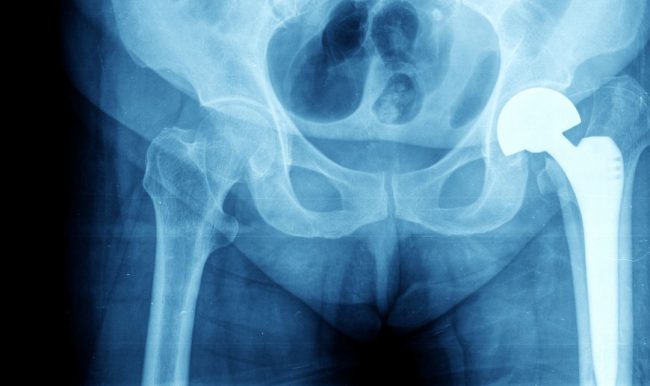

La prótesis de rodilla es la sustitución de la articulación por una pieza sintética a través de una intervención quirúrgica. Se trata de un implante que se coloca en la estructura dañada y sustituye su función, permitiendo al paciente volver a mover la articulación, eliminando cualquier dolor que pudiera tener. El motivo más habitual por…